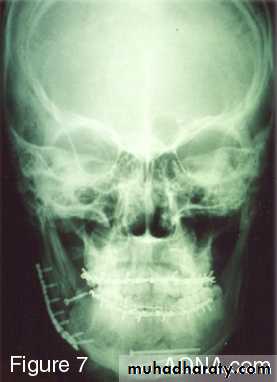

▶ Open reduction and rigid fixation (using bone palates, osteosynthesis)

• Rigid internal fixation (plating) these method use bone plates, bone screws or both to fix the fracture.

Rigid fixation

Intraossous wiringPlates and screws

Plating

If teeth are present IMF is done ; then incision is made and bone is reached either extra orally or intra orally.

The fractured ends are approximated and screw holes are made such that at least 2 screws can be placed on either side of the fracture.

The champy,s technique of plate fixation

1- Use mono cortical screw fixation ; place a minimum of 2 screws on each side of the fracture.2- The more posterior the fracture the more higher the plate should be placed . The more anterior the fracture , the closer the plate should be placed to the lower border.

3-To avoid devitalization of bone , place plates supra periosteally in atrophic edentulous mandible and extensively comminuted fracture.

In plating posterior mandible single upper border plate is enough for fixation. While in plating anterior mandible , two plates are required to help counter the torsional forces of fracture in this location.